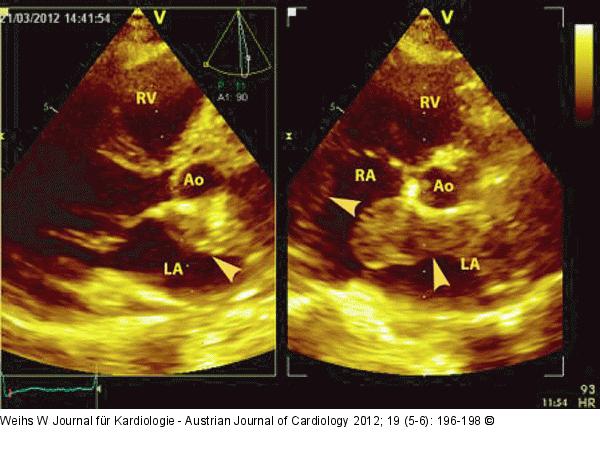

Abbildung 4: Echo Parasternaler Längs- und Querschnitt: Darstellung der Raumforderung im linken und rechten Vorhof sowie im interatrialen Septum (Pfeile). LV: linker Ventrikel; LA: linker Vorhof; RV: rechter Ventrikel; Ao: Aorta |